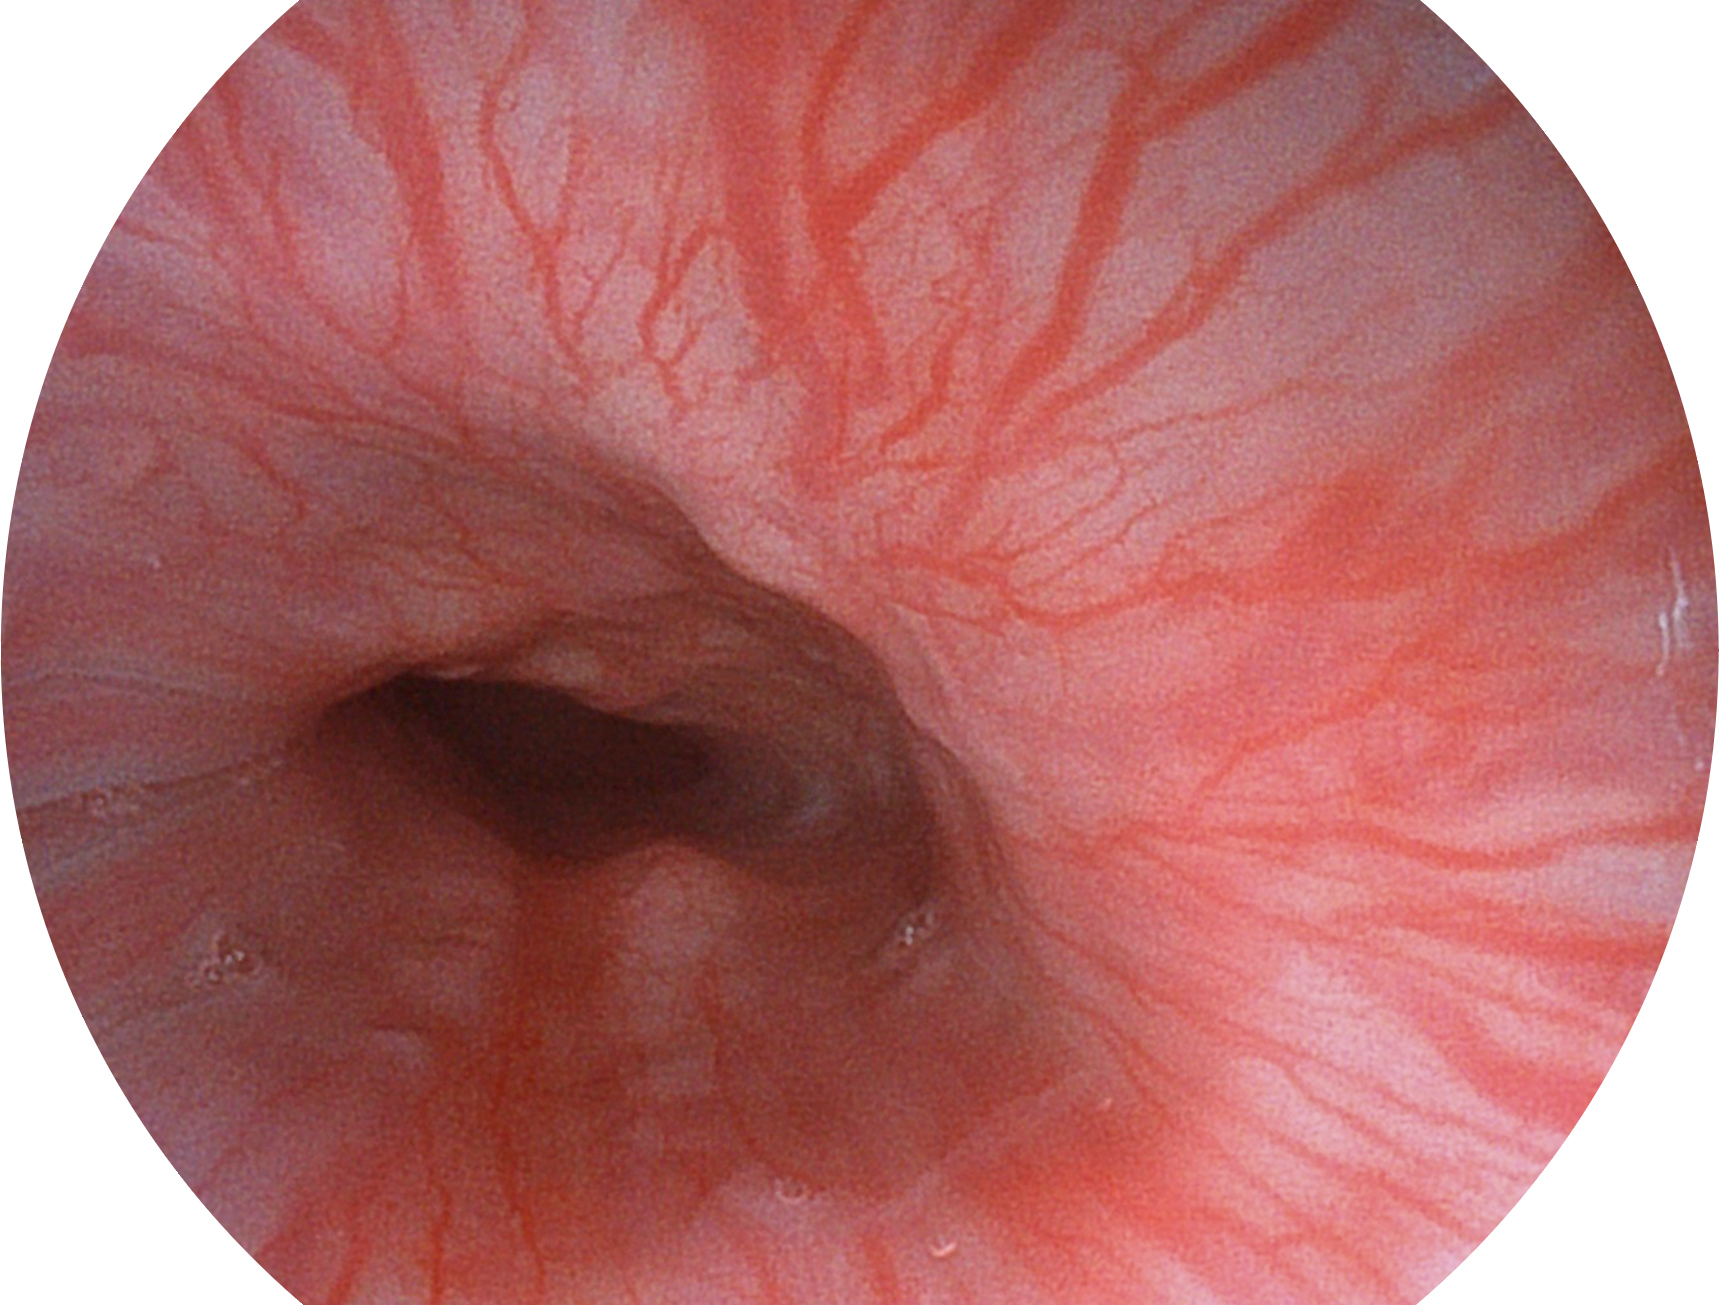

新葡的京集团8814检测站新开发的内镜染色技术,主要是基于多波长LED 光源的开发,VLS-55Q 四波长LED 光源是由四个不同颜色的LED光按照相应照明模式所规定的特定发光比例进行合束后形成,合束后形成的照明光的光谱由红光、绿光、蓝光及蓝紫光这四个不同的波段范围构成。具有更高光谱自由度,通过光谱比例的控制,实现了聚谱成像技术,英文全称为“Spectral Focused Imaging, SFI”,缩写为“SFI”和光电复合染色成像技术,英文全称为“Versatile Intelligent Staining Technology, VIST”,缩写为“VIST”。